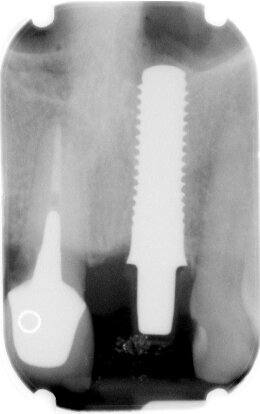

In paziente di sesso femminile ASA1, non fumatrice con ricostruzione endo-protesica su 1.1 e 2.1 si evidenzia un’irrimediabile frattura verticale di 2.1 con perdita di una estesa porzione coronale (Fig. 1), confermata dalla radiografia endorale eseguita con centratore (Fig. 2). Al sondaggio non si percepisce perdita ossea a livello circonferenziale. Nella stessa seduta si procede ad avulsione radicolare cercando di non lesionare la struttura ossea e conservando anche le limitrofe papille. Data la richiesta di estetica manifestata dalla paziente e il miglioramento di entrambe le corone cliniche si procede con l’inserimento di un’impianto endosseo secondo la tecnica postestrattiva immediata e contestuale posizionamento di provvisorio con l’unione di entrambe le corone protesiche.

Fig. 8 - Visione radiografica seguente all’inserimento dell’impianto.